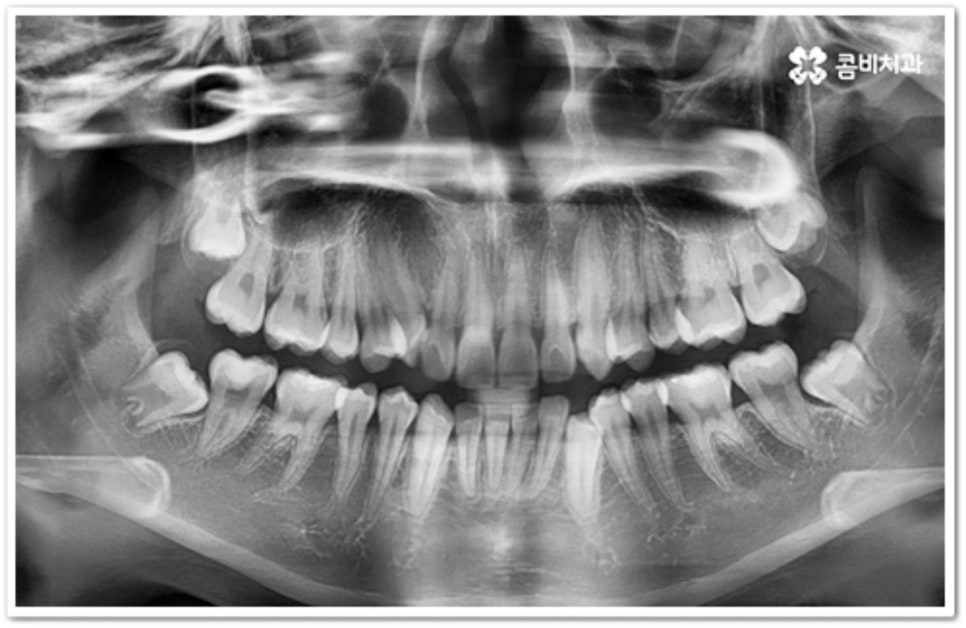

그러나 만약 덧니가 많고 부정 교합 정도가 심하거나 치아가 고르게 배열될 공간이 크게 부족하다면 덧니 발치 교정 치료를 진행하게 되는데, 이때 보통 치아 중에 기능이 가장 적은 소구치를 우선적으로 발치하게 되지만 (사진에서 확인할 수 있는 케이스) 환자분들의 상황에 따라 필요 없는 사랑니를 발치하고 어금니부터 뒤로 밀어 자리를 잡아주거나 충치 또는 짧아진 치근 등으로 심하게 손상된 치아가 있는 소구치를 우선적으로 발치하여 교정 치료를 진행하기도 하고, 필요시 임플란트와 병행하여 치료를 진행하는 경우도 있습니다. 따라서 먼저 자신의 상황에 대해서 면밀하게 검진을 받아보고 자세한 치료 계획에 대해서 의료진과 충분하게 상담해 보시는 게 좋을 거예요.

이와 같이 덧니라고 해서 치료가 다 똑같이 진행되는 것이 아니기 때문에 개개인의 치열, 교합 및 골격 형태와 턱의 구조적 특징을 명확하게 파악할 수 있는 정밀 검진 장비와 다양한 케이스 경험이 풍부한 숙련된 의료진, 체계적인 사후 관리 시스템이 있는 곳에서 진료를 받으실 것을 권유드리고 있어요.